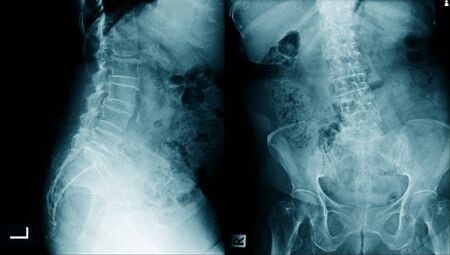

ESPONDILOSIS LUMBAR

Aunque los cambios producidos por la espondilosis se observan en toda la columna, es en la zona lumbar donde suelen producir más síntomas. El 80% de las personas van a sufrir dolores lumbares en algún momento de su vida. Aunque la espondilosis lumbar no siempre produce síntomas los más frecuentes son:

- Lumbalgia: Es el síntoma más frecuente, la causa de baja laboral más frecuente y uno de los principales motivos por los que se pide cita al médico de cabecera. Se denomina lumbalgia al dolor que se produce en la región comprendida entre la última costilla y la pelvis. Se caracteriza por un dolor que puede ser muy intenso que limita la movilidad, suele ser un proceso benigno que dura 2-3 semanas y se produce principalmente por rotura de fibras musculares ante malas posturas o esfuerzos repetidos. Otra causa de lumbalgia son los cambios inflamatorios que se producen alrededor del disco intervertebral y las articulaciones facetarias cuando presentan cambios debidos a la espondilosis.

- Ciática: Ya hemos hablado de los cambios que sufre el disco intervertebral debido a la espondilosis, cuya consecuencia final es la aparición de hernias y protusiones discales. Cuando una hernia o protusión contacta y presiona una raíz nerviosa se produce una ciática. Una ciática es un dolor intenso que desciende por la pierna y que se asocia con alteraciones sensitivas y pérdida de fuerza.

- Síndrome facetario: Las alteraciones de las facetas y la pérdida del cartílago artícular provoca dolor. El síndrome facetario se caracteriza por ser un dolor de predominio matutino asociado a rigidez. Es muy típico de este síndrome levantarse por las mañanas bloqueado de la espalda y con dolor y a medida que nos movemos y la musculatura calienta el dolor mejora.

Disco intervertebral

En el disco es donde se producen los primeros cambios que desembocaran en la espondilosis. El disco intervertebral es la almohadilla que se encuentra entre las vértebras, su misión es facilitar los movimientos de la columna y distribuir las cargas. El disco está formado por un núcleo gelatinoso rodeado de un anillo fibroso que lo contiene.

En un principio el disco pierde sus propiedades, se deshidrata y ya no transmite las cargas ni realiza los movimientos correctamente, las fibras del anillo pierden elasticidad para adaptarse a las presiones del disco se degeneran y se rompen, es cuando aparecen las protrusiones y en los casos más extremos las hernias discales.

Articulaciones facetarias

Son las articulaciones que conectan una vértebra con otra en la parte posterior. Con el avance de la espondilosis el disco intervertebral pierde altura, lo que provoca que aumente el contacto entre las articulaciones facetarias y la presión que tienen que soportar. La primera consecuencia de este cambo será la degeneración del cartílago facetario y la aparición de artrosis facetaria.

Una vez que se produce la artrosis facetaria y el movimiento produce dolor se va a producir un aumento del tamaño de la articulación para tratar de contrarrestar y reducir el movimiento doloroso, es lo que se denomina hipertofia facetaria